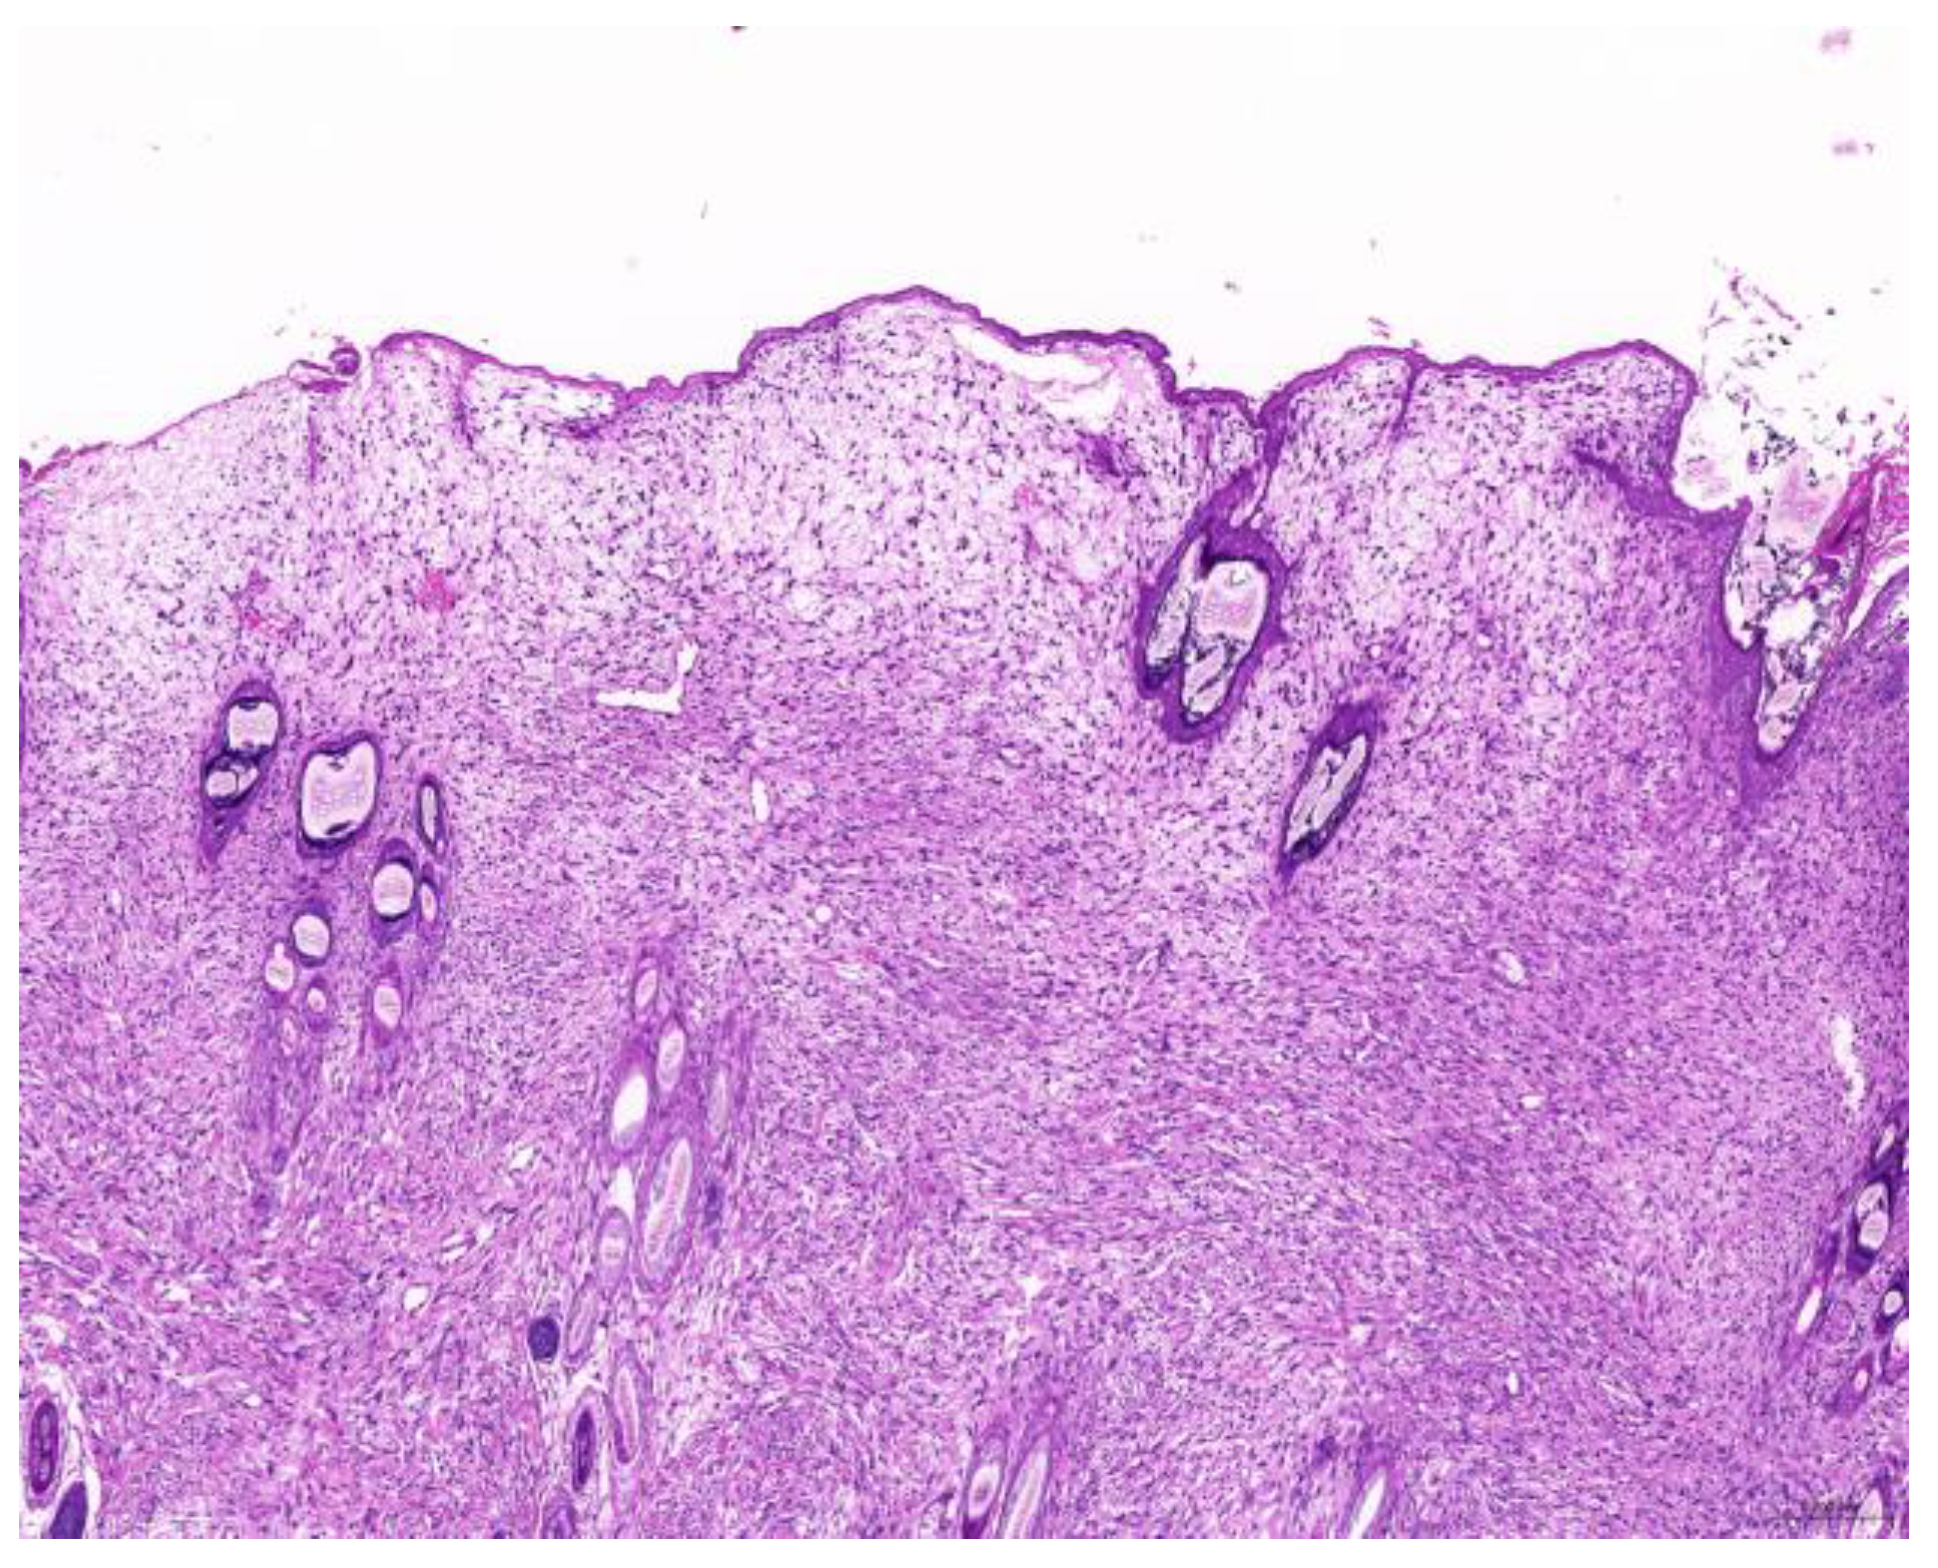

Of the 85 biopsy samples, the most commonly affected system was the integumentary system (48.2%, 41/85), followed by the reproductive system (42.4%, 36/85), the digestive system (8.2%, 7/85), and the urinary system (1.2%, 1/85) (Table 3). Of the 41 rabbits with an affected integumentary system, 39 had neoplastic and two had non-neoplastic disorders. The median age of these affected rabbits was 87 (12–149) months. There were 15 females and 26 males, with a female-to-male ratio of 0.54:1. The most common integumentary diagnosis was fibrosarcoma (29.3%, 12/41) (Figure 1), followed by trichoblastoma (19.5%, 8/41) (Figure 2), fibroma (9.8%, 4/41) (Figure 3), lipoma (7.3%, 3/41), mammary gland adenoma (7.3%, 3/41), and mammary gland adenocarcinoma (4.9%, 2/41) (Figure 4), among others. The median age of the rabbits with fibrosarcomas was 108 (54–126) months. Of the 12 cases with fibrosarcoma, 4 were females and 8 were males, with a female-to-male ratio of 0.5:1. The tumors were located on the neck, chest, abdomen, and extremities. The median age of the rabbits with fibromas was 101 (48–108) months. All four of these were males, with tumors exclusively located on the chest. Myxosarcoma was diagnosed in a 108-month-old male rabbit, with the tumor located on the left elbow (Figure 5).

Figure 2. Trichoblastoma. Neoplastic cells are arranged in trabeculae (scale bar = 500 µm). Hematoxylin and eosin staining.